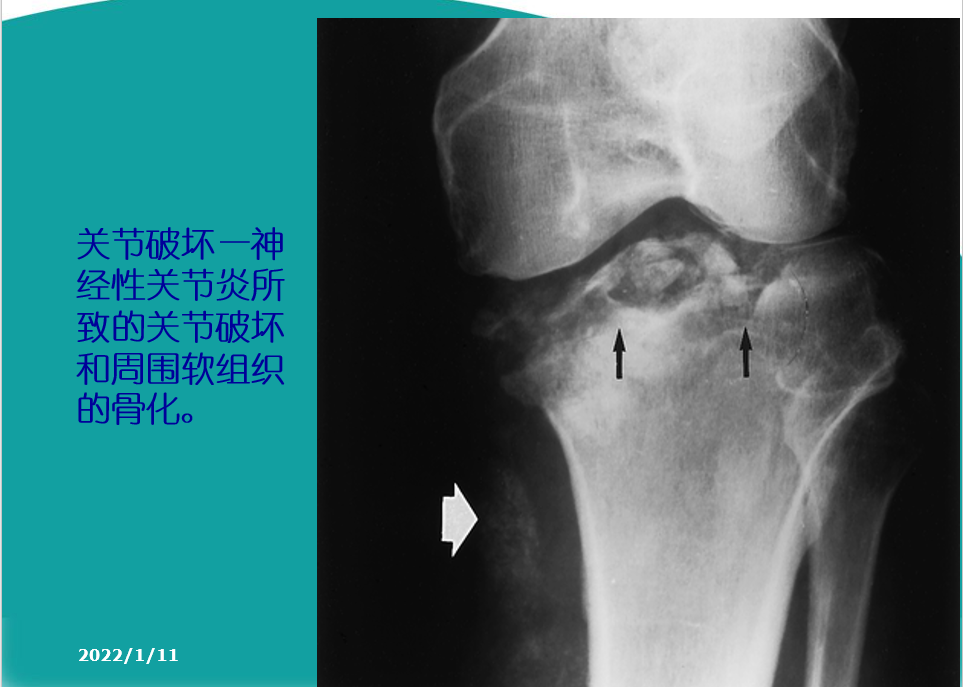

关节软骨的改变:软骨水肿、软骨囊性变、软骨变薄、磨损、软骨破坏